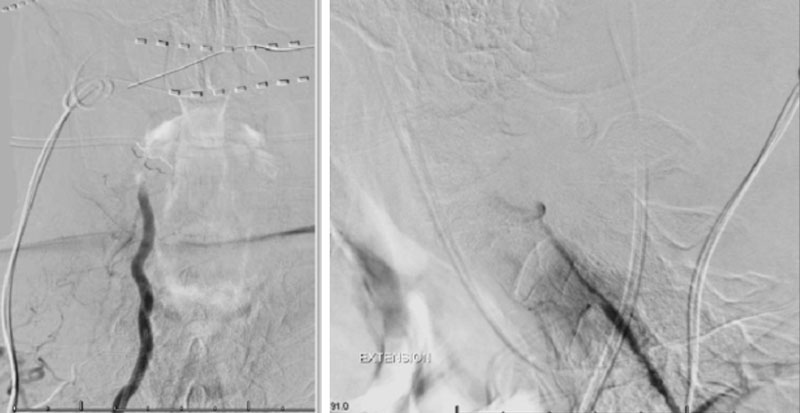

We performed conventional catheter angiography with provocative testing to reproduce his symptoms. The right Vertebral Artery is the codominant primary supply to the basilar circulation with reflux into the distal left Vertebral Artery that is occluded (Figure 3).

During neutral positioning, the vertebrobasilar circulation fills briskly from the Right Vertebral Artery. (Figure 4)

On rotation to the left, the patient experienced mild symptoms, however no significant Vertebral Artery or basilar reduction in flow was observed. On rotation to the right, the patient experiences slightly more moderate symptoms, however no significant Vertebral Artery or vascular reduction flow was observed. On hyper extension of approximately 10-15 degrees, passively performed by the patient until symptoms are reproduced, angiogram demonstrates complete occlusion of the right Vertebral Artery at approximately the C2-C1 level. (Figure 5)